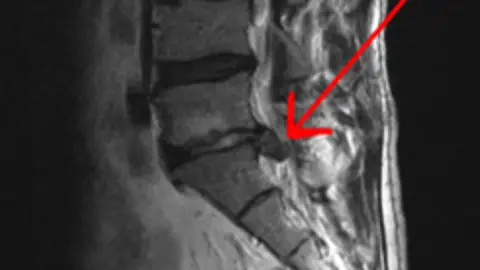

Nueva tecnología aplicada a la hernia discal con microcirugía no invasiva

Con Paco Rivero, hablamos con un especialista sobre el tema, Dr. Bernardo Mosqueira